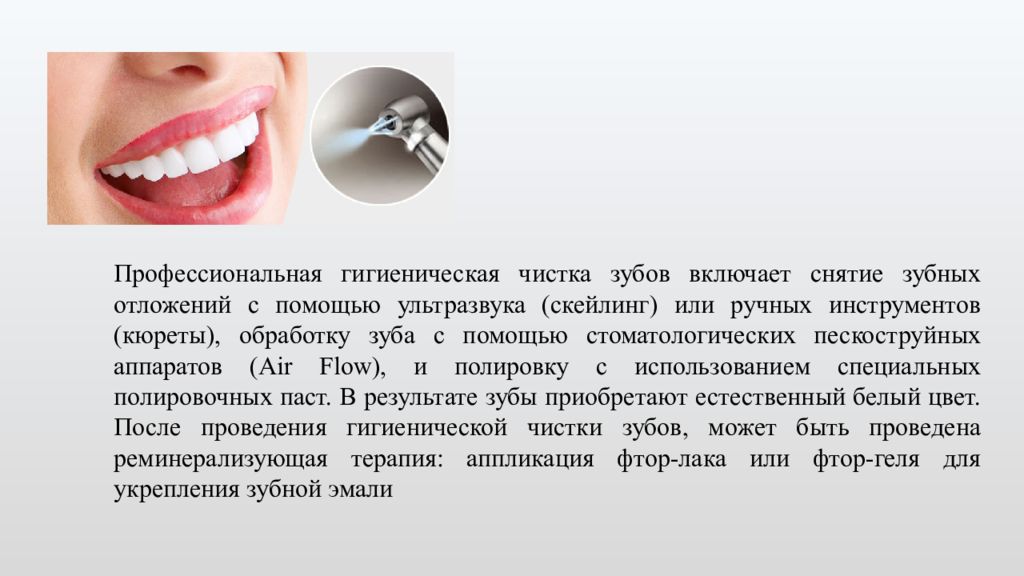

Этапы чистки зубов: Правильный уход за полостью рта

Раздел: Снимки-подсказки